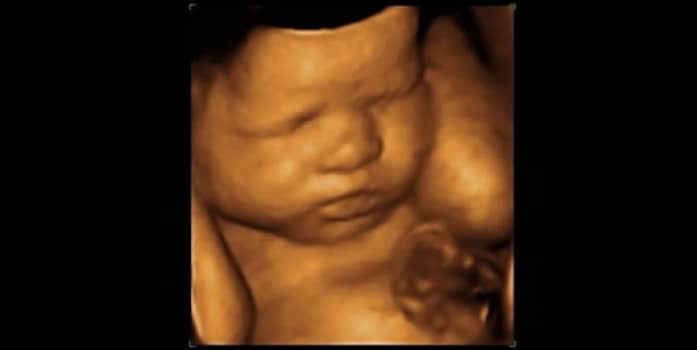

Ele é capaz de captar as imagens e transformá-las em tridimensionais, permitindo uma visualização muito mais real e nítida do bebê, quase como se fossem fotografias.

Rosto, mãos, pés e o sexo do bebê podem ser capturados com grande riqueza de detalhes.

A ultra 3D pode ser realizada em qualquer fase da gestação, mas com o avançar dos meses os detalhes observados são cada vez maiores.

As melhores imagens do bebê são obtidas a partir da 26ª semana de gravidez, pois neste período o feto já tem uma boa quantidade de tecido gorduroso e bastante líquido (o que é necessário para formação de imagens nítidas), e, seu rosto já está em formação avançada.

Confira algumas fotos de bebês feitos por ultrassom 3D: